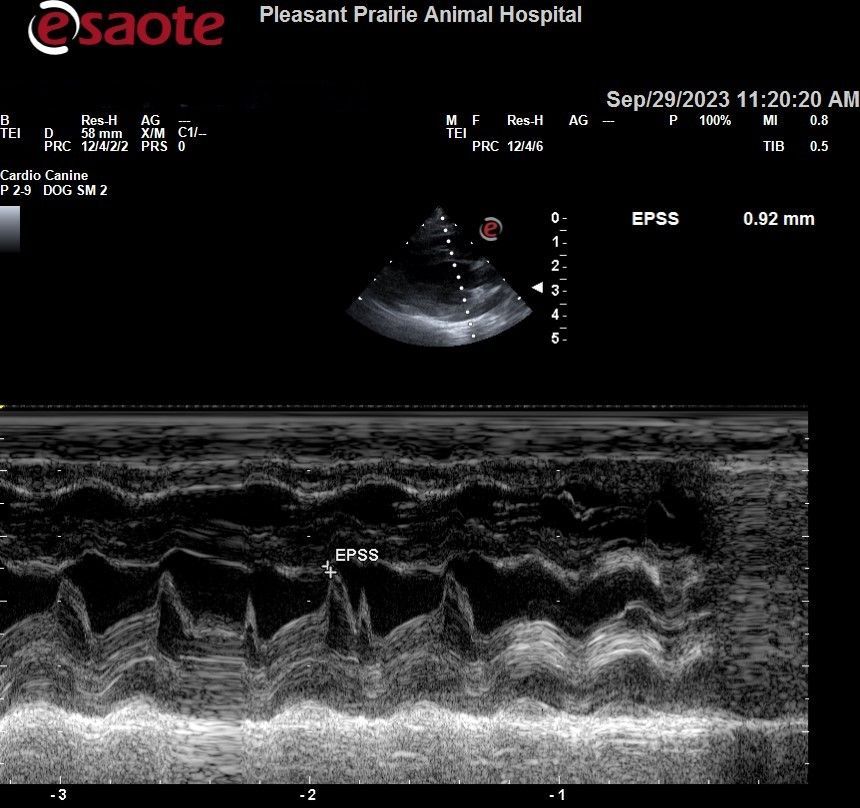

Echocardiogram (Cardiac Ultrasound)

- Used to evaluate heart size and functionality, including:

- Wall thickness

- Chamber sizes

- Valve appearance

- Contraction strength